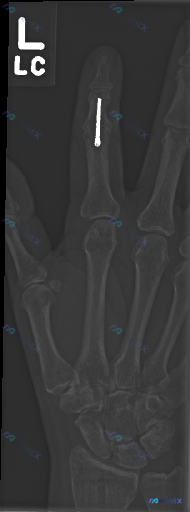

整理到一份左手正位X光片的读片资料,先不看病史,只看影像表现,大家第一眼会注意到哪些异常?下一步最想先问什么? 影像描述(精简): - 左手正位片,清晰度可 - 食指近节指骨骨干:可见一枚金属内固定钉 - 第一掌骨基底部与大多角骨之间/第一掌骨头尺侧附近:可见一类圆形/高密度游离骨块影,边缘尚光滑...